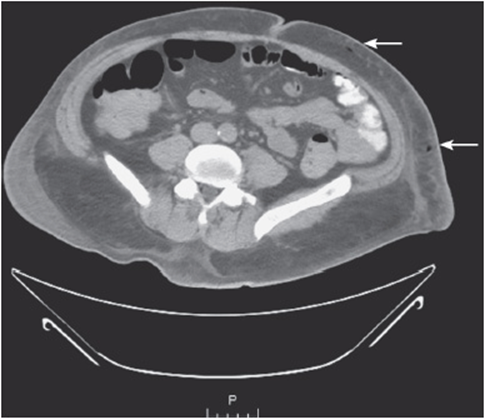

• Look for any thickening of the abdominal wall layers or any bubbles of air that could be concerning, in the right clinical scenario, for necrotizing skin and soft tissue infections (see Figure 56-1).

Figure 56-1. CT abdomen revealing abnormal air within the abdominal wall. In the right clinical scenario, this finding is suspicious for a necrotizing skin and soft tissue infection.